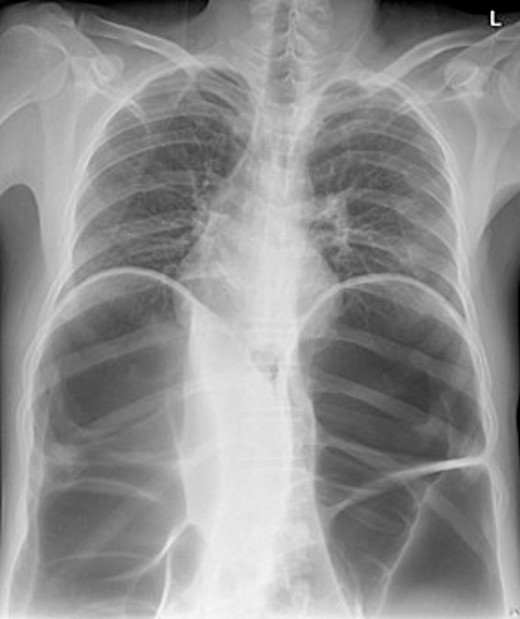

By physical examination, the patient was found to have a distended and tender abdomen along with swelling and tenderness over the left hip. The patient was investigated and found to have a bowel obstruction. The patient was later found to have an incisional hernia at the place of the prior ORIF which required surgical intervention. Below is the inspection of the patient’s abdomen at admission (Figs 1 and 2).